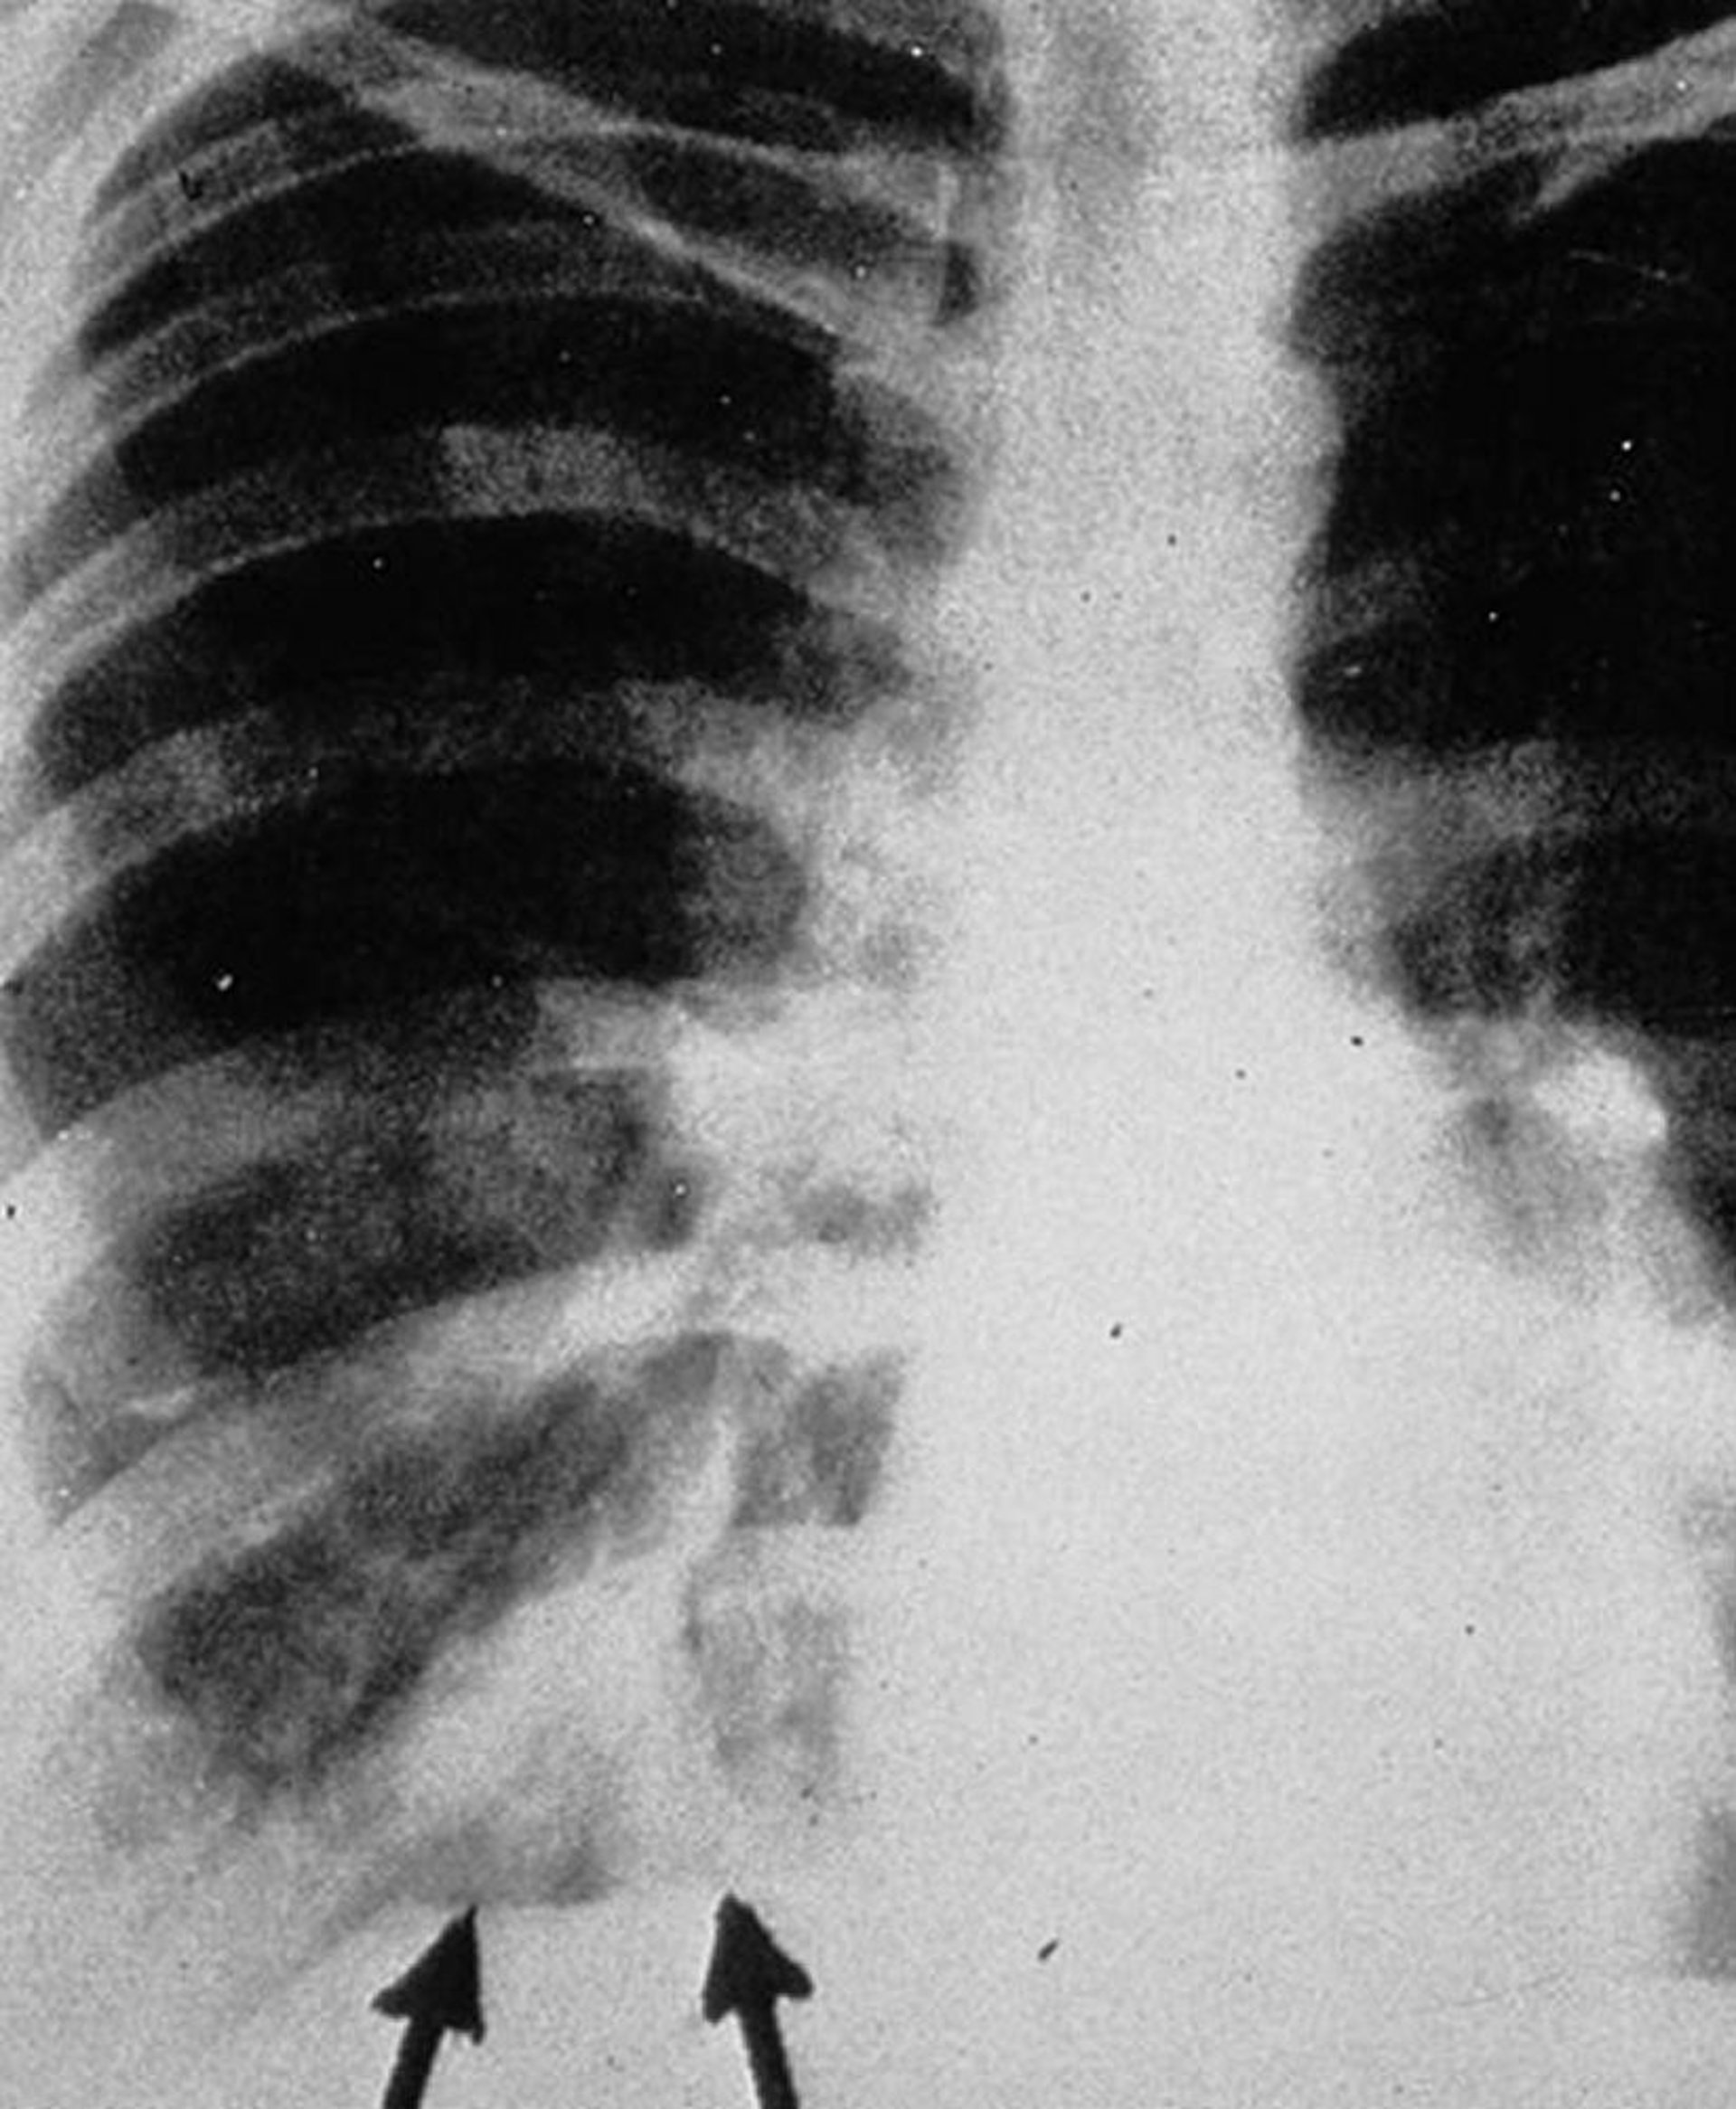

アレルギー性気管支肺アスペルギルス症

胸部X線の後前像で,気管支壁の肥厚を伴う気管支内滲出液を示す枝分かれした管状影,すなわちgloved finger影(矢印)がみられる。